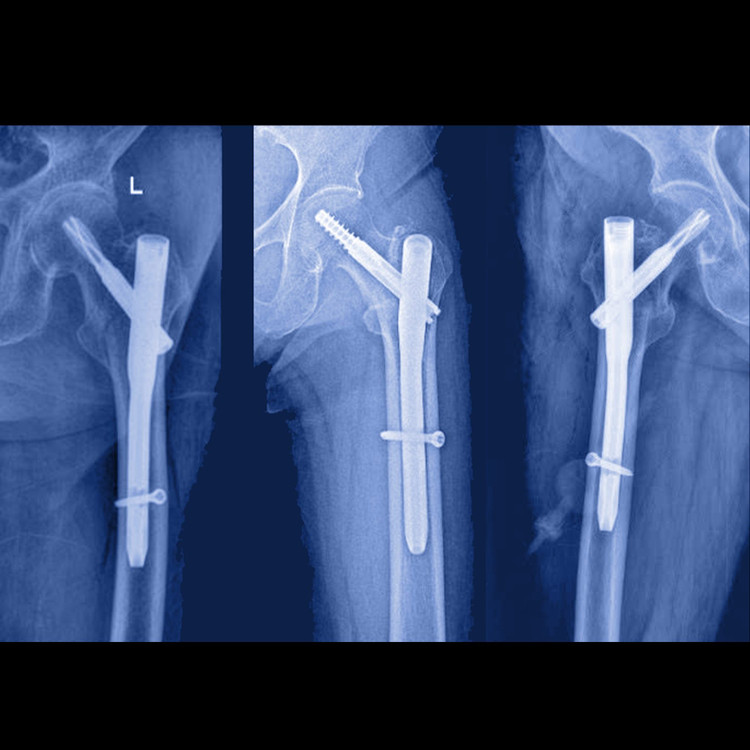

noi-xuong-1.jpg

Đóng đinh nội tủy bắt vít ổ gãy - Ảnh BVCC

Với kỹ thuật nội soi, bác sĩ chỉ cần rạch các đường mổ nhỏ 2-3 cm, đóng đinh nội tủy và bắt vít cố định ổ gãy.

3 ca mổ diễn ra thuận lợi, thời gian mổ khoảng 40-60 phút. Người bệnh hồi tỉnh tốt, ít đau, có thể tập phục hồi chức năng ngay tại giường ngay ngày đầu sau mổ, hạn chế tối đa biến chứng do nằm lâu. Sau khoảng 2 ngày, các cụ đã có thể tỳ đè, tập đi với dụng cụ hỗ trợ và xuất viện sau 5-7 ngày.